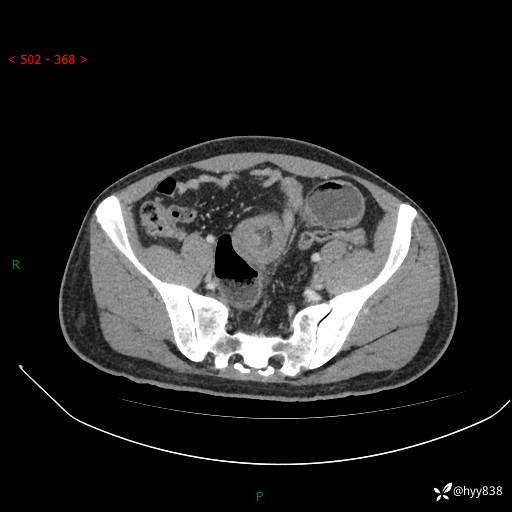

年轻男性,腹痛5月余。除了肠梗阻,你还能看到什么---结果公布~

主诉:腹痛5月余。

现病史:患者于5月前无明显诱因开始出现腹痛,上明显,为间断性胀痛不适,无畏寒发热,无心慌气促等特殊不适,遂来我院。我院门诊遂以“腹痛原因待查”收入我科。 起病以来,患者精神、饮食、睡眠欠佳,大小便正常。体力体重无明显变化。

腹部CT增强扫描(动脉期+静脉期)